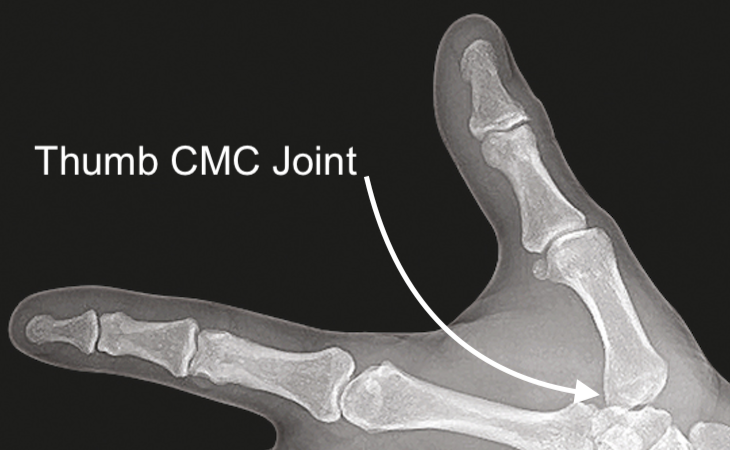

The Thumb CMC Joint provides an articulation between:

• First Metacarpal: The primary bone of the thumb connecting to the carpals.

• Trapezium: One of the carpal bones.

• CMC joint X ray